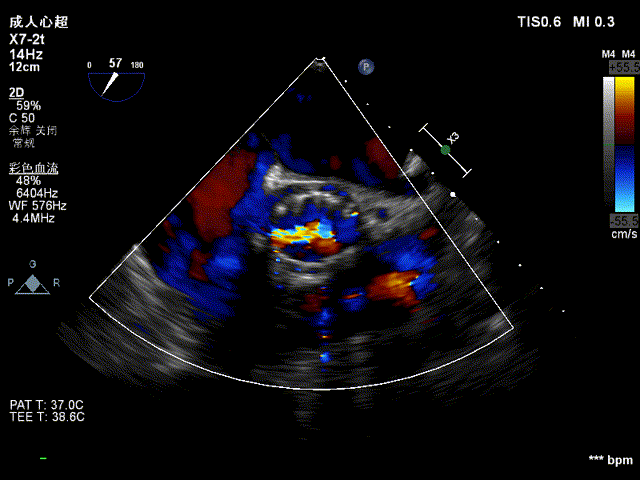

超声看位置合适,无反流

患者压差从64mmHg降为4mmHg,效果显著。